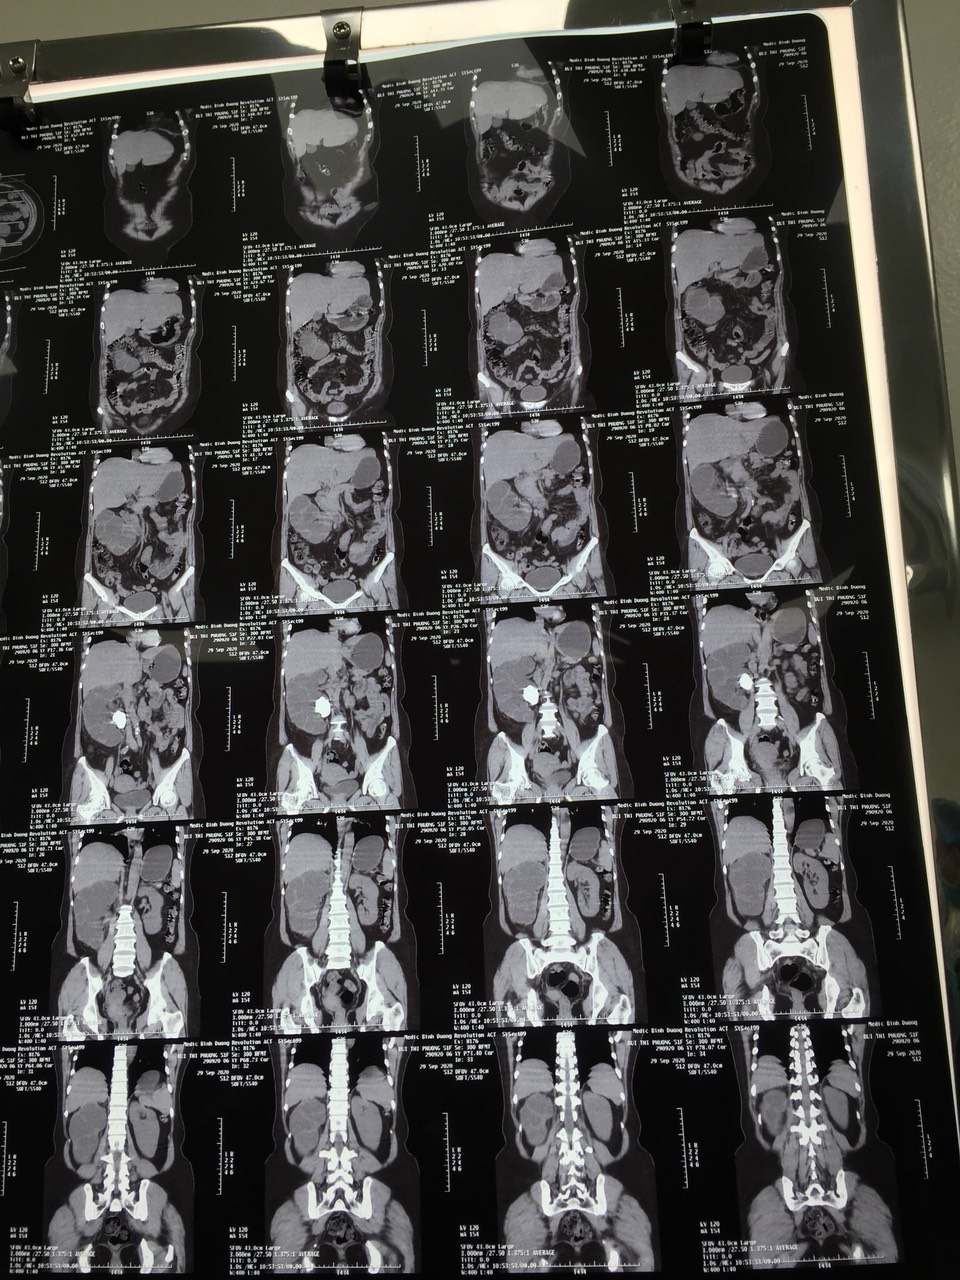

Trước đó, cô P. nhập viện trong tình trạng đau tức hông, lưng, khó tiểu. Qua thăm khám, kết hợp với kết quả siêu âm, chụp CT, các bác sĩ khoa Ngoại đã chẩn đoán bệnh nhân bị sỏi san hô thận trái kích thước lớn gây biến chứng giãn đài bể thận, khiến thận bị ứ nước và được chỉ định phẫu thuật lấy toàn bộ sỏi ra ngoài. Tuy nhiên, ca phẫu thuật có thể gặp nhiều khó khăn và rủi ro do cô P. có tiền sử tăng huyết áp và tiểu đường.

Trong khi tiến hành phẫu thuật, các bác sĩ đã bóc tách nhiều viên sỏi với các kích thước khác nhau, trong đó có những viên kích thước lớn, các nhánh sỏi bám chặt vào ống thận. Sau hai giờ phẫu thuật, ca mổ đã thành công. Sau khi phẫu thuật, cô P. đang được tiếp tục điều trị bằng kháng sinh phối hợp liều cao. Hiện tại sức khỏe cô P. đã ổn định và có thể xuất viện trong vài ngày tới.